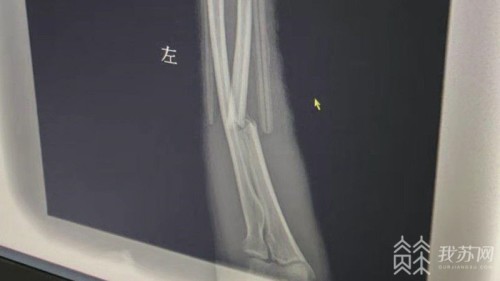

医院资料显示,事故中倪先生左小臂骨折。在倪先生入院治疗的同时,已经有路过居民报警,警方赶到现场后对事故现场进行了清理调查,并且找到了倪先生遗失在车内的手机。倪先生说,交警发了信息给他老婆。